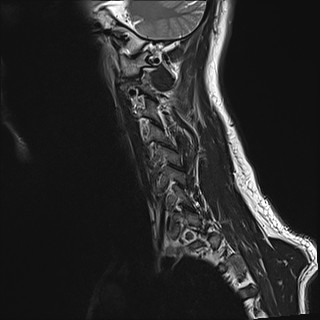

Wirbelsäule HWS

t1_tse_sag